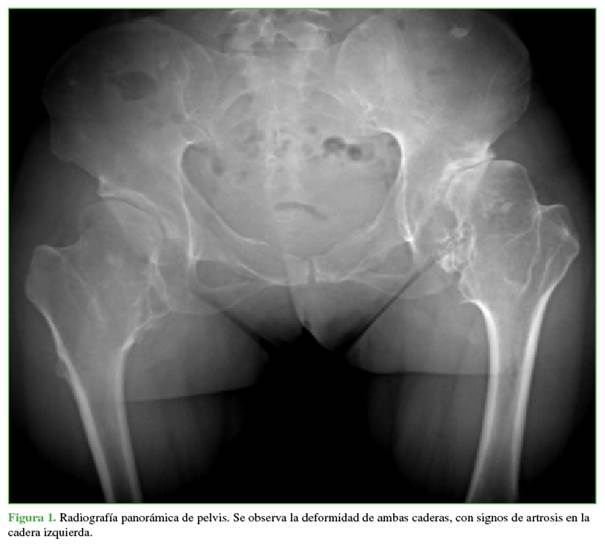

Mujer de 42 años de edad, con antecedentes familiares de EMH en su línea paterna que consultó, por primera vez, por coxalgia izquierda de dos años de evolución. Refería un dolor intenso con la carga de peso y limitación de las actividades cotidianas. La movilidad de la cadera era de 120º de flexión, 30º de abducción y limitación de las rotaciones. El puntaje de cadera de Harris9 era de 75. En la radiografía de pelvis, se observó una displasia bilateral de cadera con subluxación de la cabeza femoral y protuberancias óseas (exostosis) en ambos trocánteres menores hacia la cabeza femoral (Figura 1). La cadera izquierda tenía un ángulo cervico-diafisario de 165º, incongruencia acetabular y signos artrósicos que eran más evidentes en la tomografía computarizada (Figura 2). En las radiografías de rodillas y tobillos, se visualizaban las múltiples exostosis y una anquilosis tibio-peronea (Figura 3).